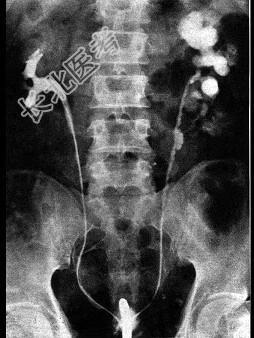

- 单项选择题关于泌尿系结核时尿频产生的原因,下列哪一项是错误的 ( )

A、结核性脓尿刺激膀胱黏膜

B、结核病变延及膀胱

C、膀胱挛缩

D、病侧输尿管完全闭塞

E、膀胱痉挛